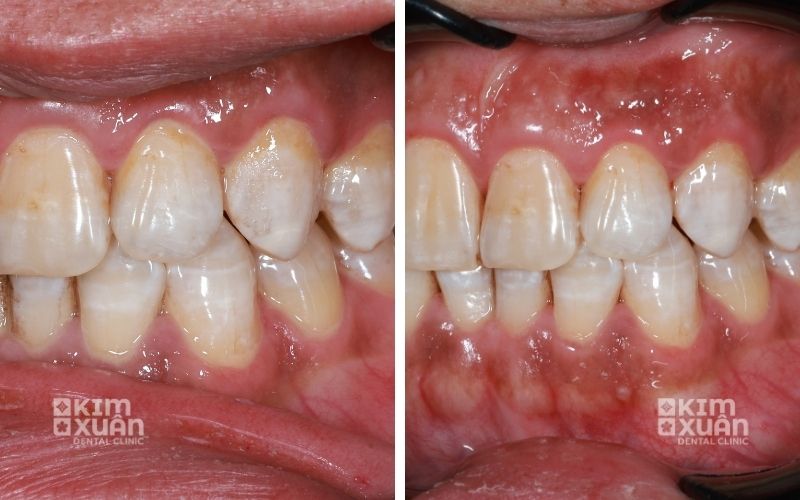

6.1. Cạo vôi răng - làm sạch chuyên sâu

Bác sĩ sẽ tiến hành lấy sạch mảng bám và cao răng bám quanh chân răng và dưới viền nướu. Đây là bước quan trọng giúp giảm viêm, hạn chế vi khuẩn và tạo điều kiện để nướu phục hồi khỏe mạnh.